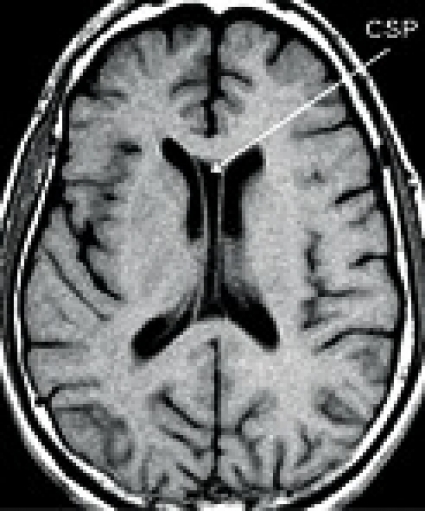

Saeptum pellucidum består av två tunna vävnadsskikt som bildar den mediala väggen mellan sidoventriklarna. Under fosterlivet är vävnadsskikten separerade, men sammanlöds före födseln eller under barndomen. Med cavum saepti pellucidi avses en hålbildning mellan vävnadsskikten med inträde av likvor (Figur 2 [ned till höger]). Prevalensen av CSP i befolkningen varierar mellan olika studier, men den är sannolikt cirka 5 procent [34]. Flera studier har visat att förekomst av CSP är överrepresenterad hos professionella boxare, där prevalensen är 10–20 procent [32], och ses framför allt tillsammans med generell atrofi. Emellertid finns det ingen studie som funnit ett signifikant samband mellan CSP och kliniska symtom [32], och vissa forskare har därför ställt frågan om CSP är en medfödd anomali utan klinisk signifikans [35, 36].